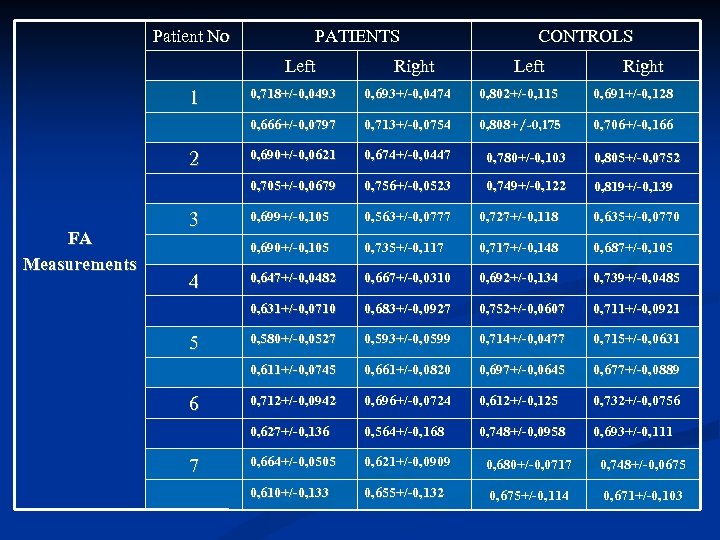

Comparing (FA) measurements, between controls and patients we found that FA measurements in patients were lower than in the age matched healthy subjects. A further decrease in FA measurements was also noticed with disease progression on the F/U study. Using fiber tractography we visualized the CST tract in healthy volunteers as well as ALS patients. A small number of patients, especially those with definite ALS, showed a visibly decreased volume of CST fibre bundles

Comparing (FA) measurements, between controls and patients we found that FA measurements in patients were lower than in the age matched healthy subjects. A further decrease in FA measurements was also noticed with disease progression on the F/U study. Using fiber tractography we visualized the CST tract in healthy volunteers as well as ALS patients. A small number of patients, especially those with definite ALS, showed a visibly decreased volume of CST fibre bundles

Patient No PATIENTS Left Right CONTROLS Left Right FA Measurements 7 0, 808+/-0, 175 0, 706+/-0, 166 0, 690+/-0, 0621 0, 674+/-0, 0447 0, 780+/-0, 103 0, 805+/-0, 0752 0, 756+/-0, 0523 0, 749+/-0, 122 0, 819+/-0, 139 0, 699+/-0, 105 0, 563+/-0, 0777 0, 727+/-0, 118 0, 635+/-0, 0770 0, 735+/-0, 117 0, 717+/-0, 148 0, 687+/-0, 105 0, 647+/-0, 0482 0, 667+/-0, 0310 0, 692+/-0, 134 0, 739+/-0, 0485 0, 683+/-0, 0927 0, 752+/-0, 0607 0, 711+/-0, 0921 0, 580+/-0, 0527 0, 593+/-0, 0599 0, 714+/-0, 0477 0, 715+/-0, 0631 0, 661+/-0, 0820 0, 697+/-0, 0645 0, 677+/-0, 0889 0, 712+/-0, 0942 0, 696+/-0, 0724 0, 612+/-0, 125 0, 732+/-0, 0756 0, 627+/-0, 136 6 0, 713+/-0, 0754 0, 611+/-0, 0745 5 0, 691+/-0, 128 0, 631+/-0, 0710 4 0, 802+/-0, 115 0, 690+/-0, 105 3 0, 693+/-0, 0474 0, 705+/-0, 0679 2 0, 718+/-0, 0493 0, 666+/-0, 0797 1 0, 564+/-0, 168 0, 748+/-0, 0958 0, 693+/-0, 111 0, 664+/-0, 0505 0, 621+/-0, 0909 0, 680+/-0, 0717 0, 748+/-0, 0675 0, 610+/-0, 133 0, 655+/-0, 132 0, 675+/-0, 114 0, 671+/-0, 103

Patient No PATIENTS Left Right CONTROLS Left Right FA Measurements 7 0, 808+/-0, 175 0, 706+/-0, 166 0, 690+/-0, 0621 0, 674+/-0, 0447 0, 780+/-0, 103 0, 805+/-0, 0752 0, 756+/-0, 0523 0, 749+/-0, 122 0, 819+/-0, 139 0, 699+/-0, 105 0, 563+/-0, 0777 0, 727+/-0, 118 0, 635+/-0, 0770 0, 735+/-0, 117 0, 717+/-0, 148 0, 687+/-0, 105 0, 647+/-0, 0482 0, 667+/-0, 0310 0, 692+/-0, 134 0, 739+/-0, 0485 0, 683+/-0, 0927 0, 752+/-0, 0607 0, 711+/-0, 0921 0, 580+/-0, 0527 0, 593+/-0, 0599 0, 714+/-0, 0477 0, 715+/-0, 0631 0, 661+/-0, 0820 0, 697+/-0, 0645 0, 677+/-0, 0889 0, 712+/-0, 0942 0, 696+/-0, 0724 0, 612+/-0, 125 0, 732+/-0, 0756 0, 627+/-0, 136 6 0, 713+/-0, 0754 0, 611+/-0, 0745 5 0, 691+/-0, 128 0, 631+/-0, 0710 4 0, 802+/-0, 115 0, 690+/-0, 105 3 0, 693+/-0, 0474 0, 705+/-0, 0679 2 0, 718+/-0, 0493 0, 666+/-0, 0797 1 0, 564+/-0, 168 0, 748+/-0, 0958 0, 693+/-0, 111 0, 664+/-0, 0505 0, 621+/-0, 0909 0, 680+/-0, 0717 0, 748+/-0, 0675 0, 610+/-0, 133 0, 655+/-0, 132 0, 675+/-0, 114 0, 671+/-0, 103

Mean FA Measurements Patients Controls Left Right 0, 661+/- 0, 08 0, 662+/-0, 07 0, 730+/-0, 09 0, 717+/-0, 08

Mean FA Measurements Patients Controls Left Right 0, 661+/- 0, 08 0, 662+/-0, 07 0, 730+/-0, 09 0, 717+/-0, 08